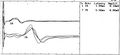

- Potenziale Evocato della Radice Trigeminale.jpg 378 × 220; 28 KB